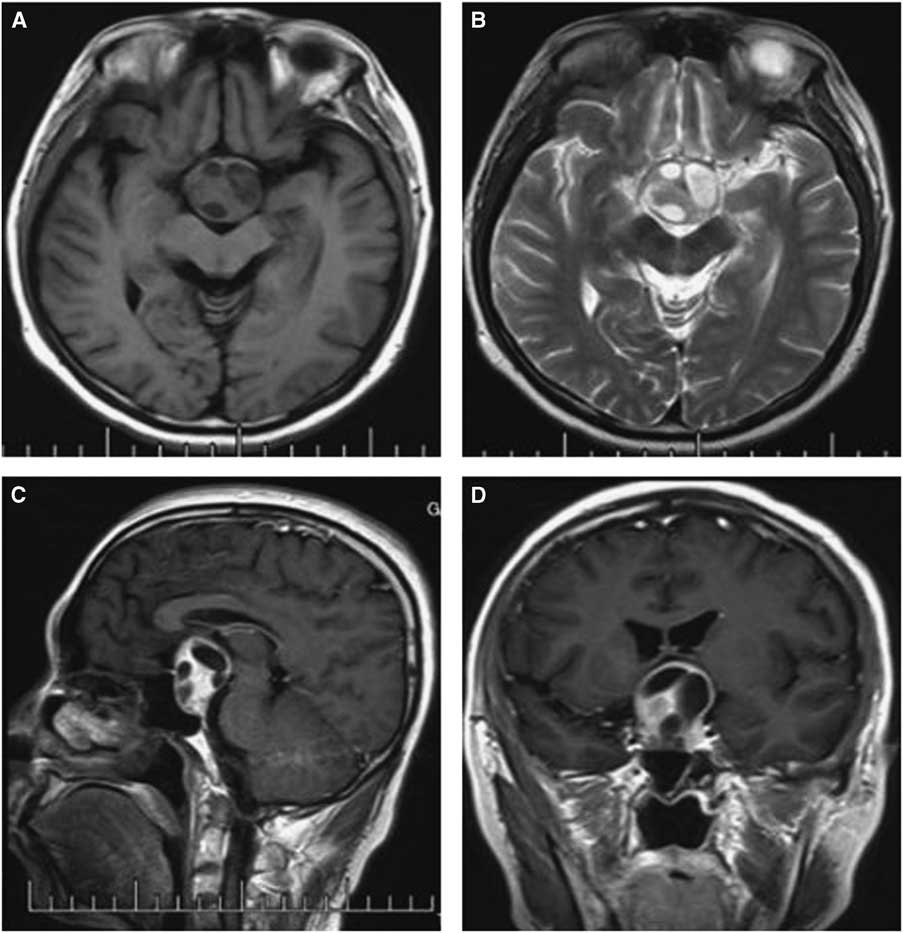

Computed tomography and MRI were performed for each patient preoperatively. Of the PAs, two were microadenomas diagnosed on dynamic contrast-enhanced scan of the sellar region with MRI. The others were macroadenomas. The tumors were mainly located in the intra- and suprasellar areas, except for four cases that involved the parasellar region. Among these cases, two were grade 3 on the Knops scale, whereas the other two were grade 4. The typical imaging of PA associated with RCC was that a cyst-like signal with no contrast enhancement was indicated on MRI with an obvious PA, and the cyst was usually enclosed by the PA or adjacent to the adenoma, as shown in case 3 (Figure 1). However, it was occasionally difficult to identify the two different signal intensities between the PA and RCC, as indicated in case 1 (Figure 2). The 15 patients were all initially diagnosed with PAs or PAs with cystic change or apoplexy of PAs.

Figure 2 Preoperative and postoperative MRI scans of case 1. Axial T2-weighted (A) images revealing uneven signal intensity in the pituitary measuring approximately 4 mm in greatest diameter. (B) A contrast-enhanced sagittal image showing obvious enhancement of the pituitary, but identifying two different entities was difficult. (C) Dynamic contrast-enhanced image demonstrating a delayed-enhancement region on the left of the pituitary, with the pituitary stalk displaced slightly to the right; The postoperative images showed the tumor was resected completely (D-F).